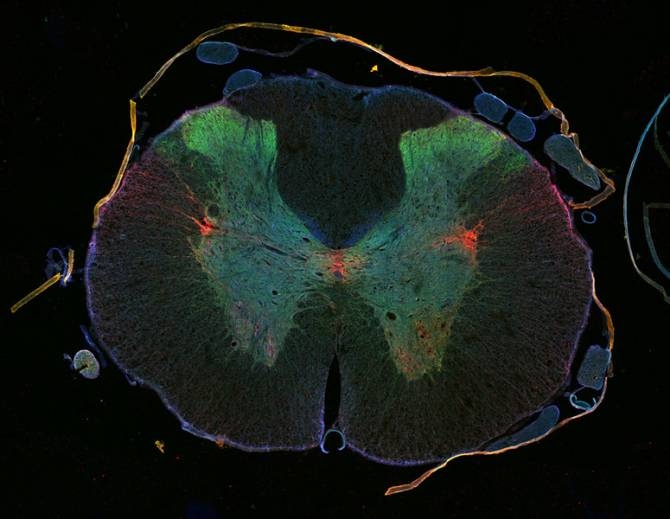

Los daños en la médula espinal raramente sanan porque las células nerviosas afectadas no consiguen regenerarse. Sus largas fibras nerviosas no logran volver a crecer debido al tejido cicatricial y a procesos moleculares dentro de los nervios. La inesperada capacidad de un fármaco anticáncer para promover la regeneración de la médula espinal podría contribuir a cambiar esta situación.

En estudios animales, ese medicamento, la epotilona, redujo la formación de tejido cicatricial en heridas de la médula espinal, y estimuló el crecimiento en células nerviosas dañadas.

Ambas cosas promovieron la regeneración neuronal y mejoraron las capacidades motoras de los animales.